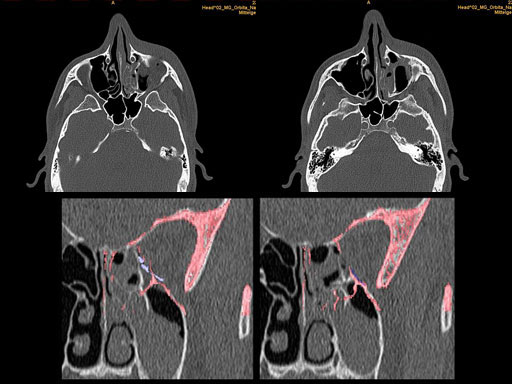

Clinical case

30 year old male patient with fracture of left orbital floor and medial wall.

Provided by Dr Dr Marc C Metzger, Freiburg, Germany.